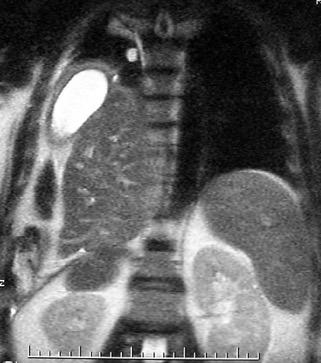

Elevación bilateral por riñones poliquísticos. Hernia hiatal ¡Sin gas en abdomen!